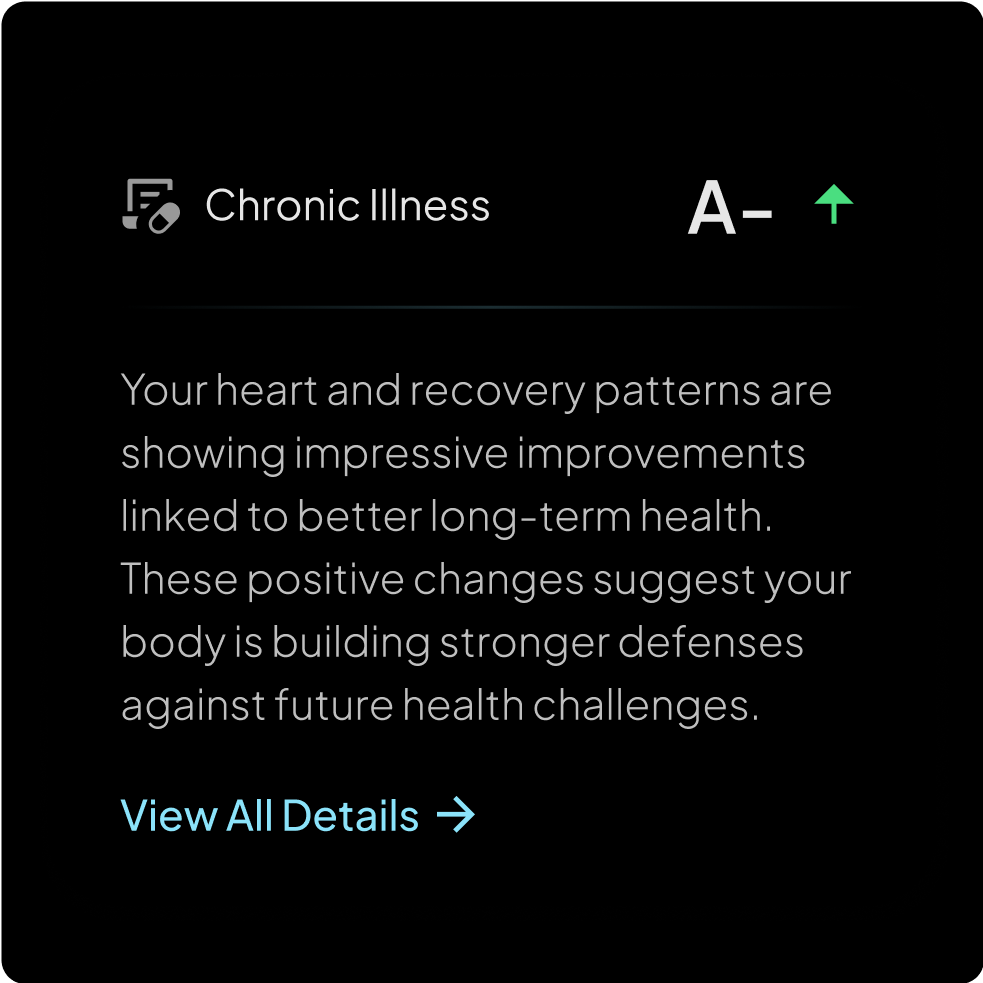

Chronic illness detection

May indicate the

onset of an illness

Identify potential health issues early and take action before they become serious.

By analyzing your body’s signals, Hume Band may detect early signs of illness—helping you take action before small issues become big problems

By analyzing your body’s signals, Hume Band may detect early signs of illness—helping you take action before small issues become big problems

We constantly scan your biometrics to detect early signs of stress, immune decline, inflammation, and recovery delays—so you can act before illness takes hold.